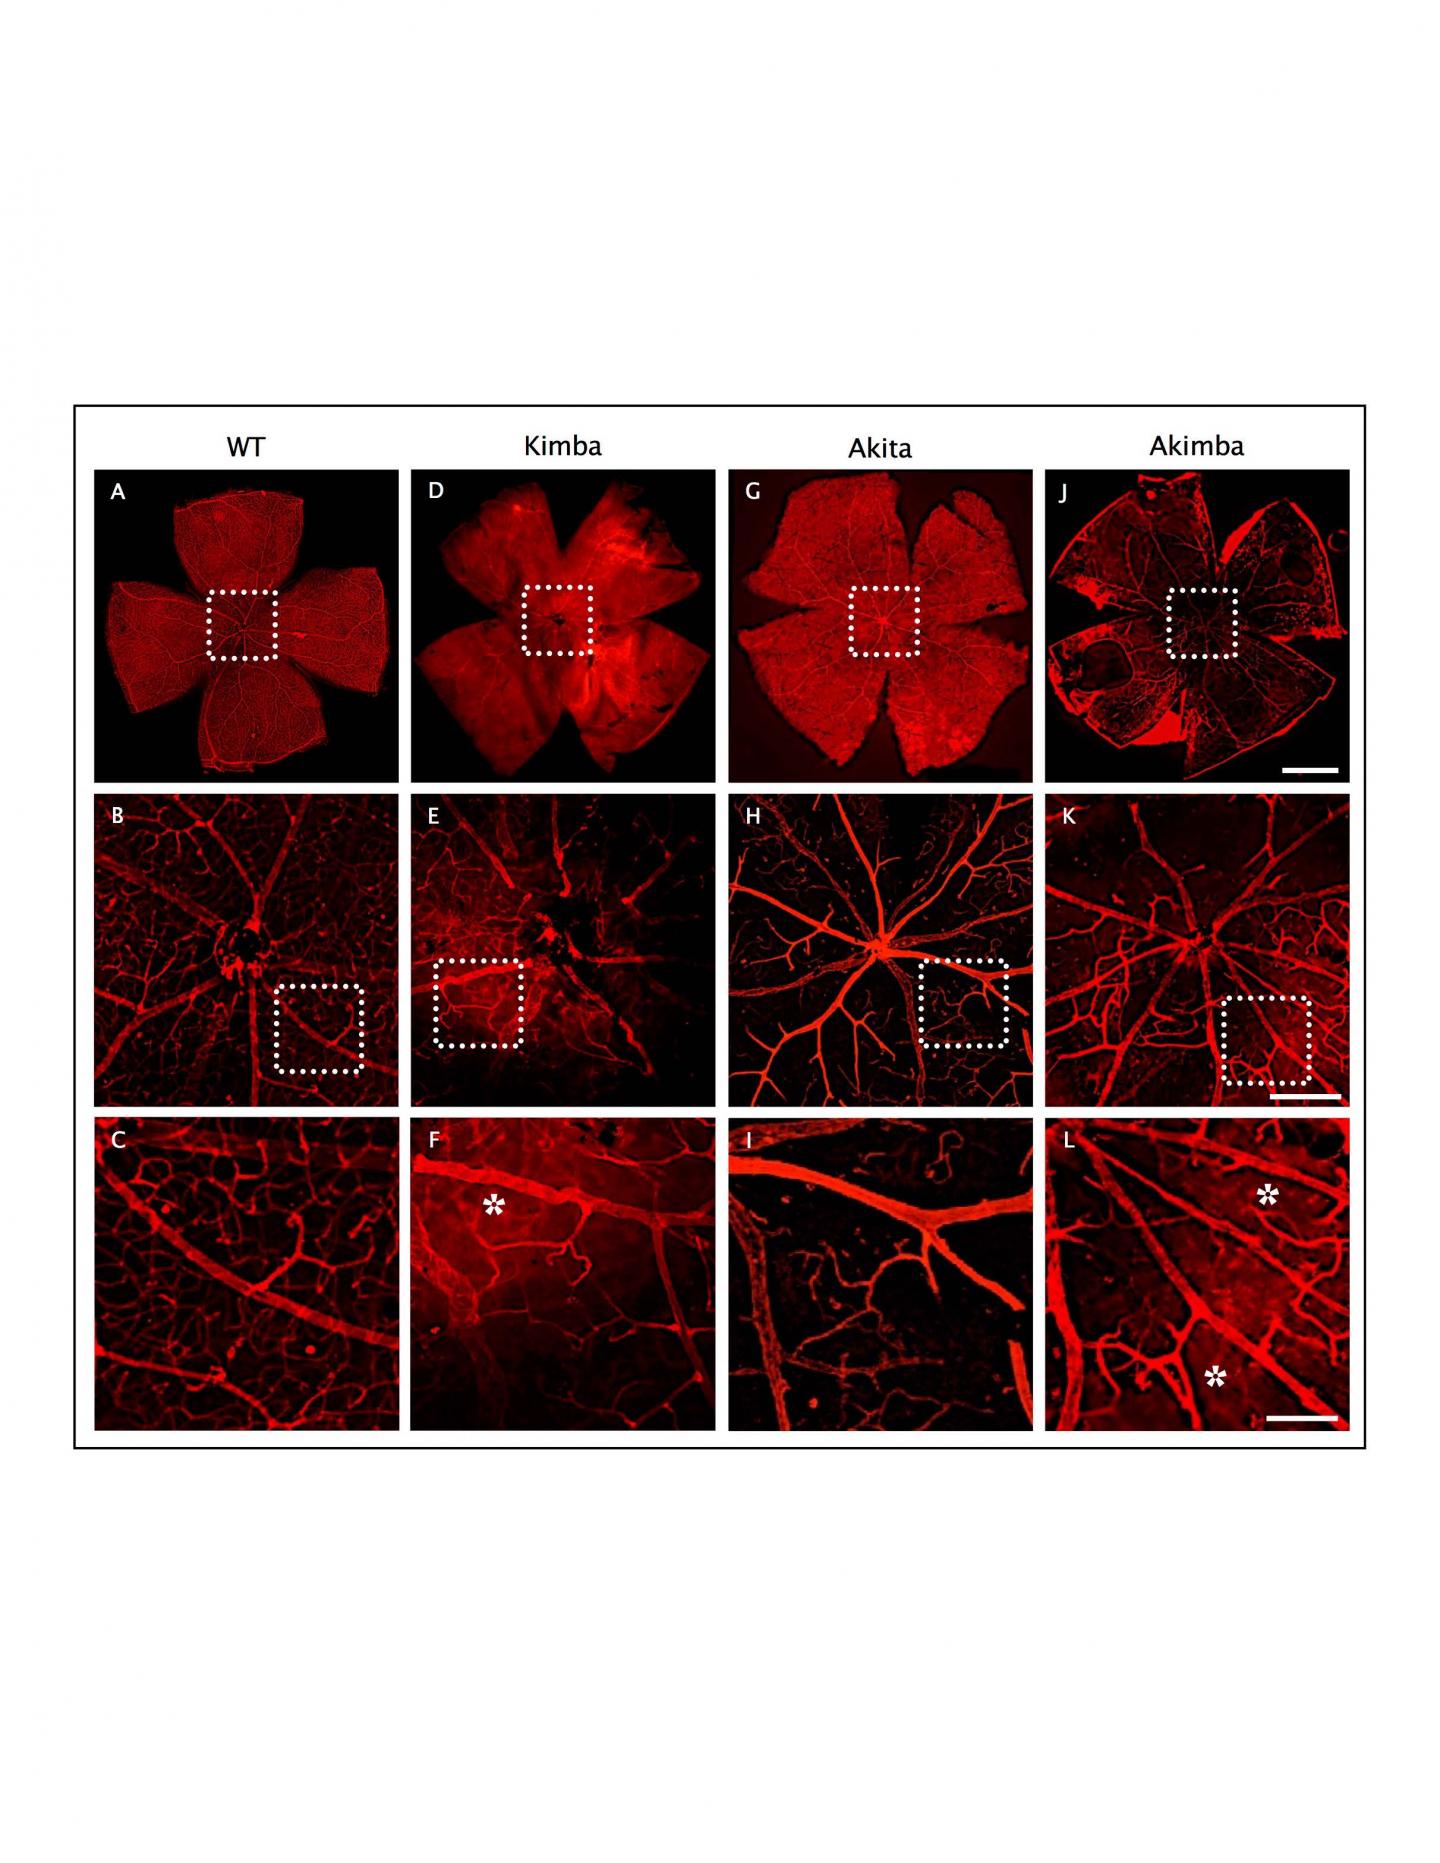

Loss of retinal capillary density and vessel leakage in Akimba mice. Isolectin-GS IB4 staining on retinal flat mount showed normal vascular bed and uniform capillary distribution in WT (A-C) mouse, which was reduced markedly in Kimba (D-F) Akita - (G-I) and significantly higher in Akimba (J-L) mice. Disruption of the capillary network was noted especially around the optic disk of Akimba (K) retina.